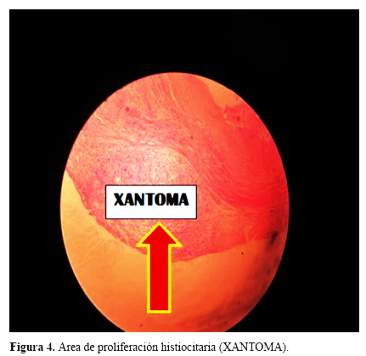

Al explorar los miembros inferiores, llamó poderosamente la atención el volumen de las regiones aquilianas aumentado y en forma de conos invertidos por la presencia de xantomas (figura 3 (A y B)). Se efectuó biopsia de la región aquiliana que mostró el tendón alterado con un área de proliferación histiocitaria en relación a lesión xantomatosa (figura 4), y la arquitectura del tendón reemplazada por tejido mixoide (figura 5).

Los xantomas tendinosos aquilianos, biopsiados mostraron la naturaleza de la enfermedad, al igual que la presencia del arco senil tempranamente aparecidos, antes de los 30 años, las cataratas, la presencia de xantoma en el cuerno ventricular derecho por la especialidad y la osteoporosis estarían indicando un estado avanzado de la enfermedad por XCT. El estudio con resonancia magnética del cerebro (RM), puso en evidencia los cambios morfológicos del tejido cerebral, asi como , la penetrancia del colagenol en estructuras específicas empleando la incidencia del FLAIR.

La presencia de los hallazgos oftalmológicos y las características morfológicas de las regiones aquilianas permitieron sospechar clínicamente de la la presencia de xantomatosis que se confirmó mediante los resultados histopatológicos de la biopsia efectuada. Los resultados de la exploración neurológica mostraron un estado demencial severo asociado a definidas alteraciones de la función cerebelosa.